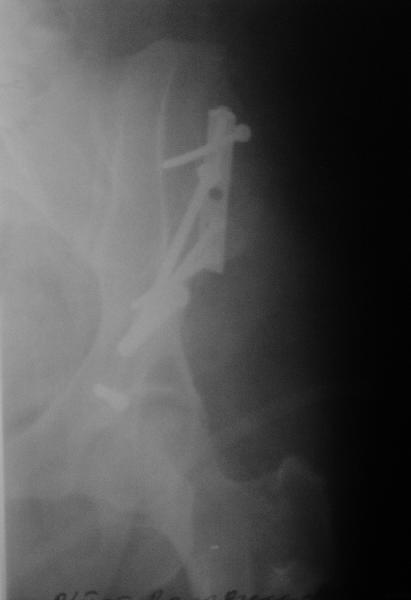

4. КТ таза абсолютно необходимо, хотя по рентгенограмме таза похоже, что кусок крыла левой подвздошной кости не прирос вообще и лежит отдельно, сместившись кпереди.

Выполнена реконструкция крыла левой подвздошной кости, грыжесечение через подвздошно-бедренный доступ. 2 фрагмента подвздошной кости, грыжа выходит между ними (см. картинки). Грыжевой мешок, спаянный с ПЖК, подвздошной костью, вскрыт, его содержимое (петли кишечника) вправлено в брюшную полость. Грыжевой мешок выделен, иссечен, наложены два ряда отдельных швов на брюшину. Отломки подвздошной кости стянуты друг с другом, зафиксированы 1/3-трубчатой пластиной и винтами к телу подвздошной кости (см. рентгенограммы). Дефект подвздошной кости был закрыт практически полностью. Решено не применять сетку. Иссечен лоскут истонченной кожи 15 на 8 см.